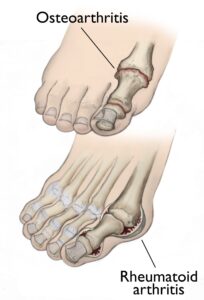

(Top) Osteoarthritis that has progressed to bone rubbing on bone and bone spurs. (Bottom) Swollen, inflamed synovium and joint deformity are signs of rheumatoid arthritis.

Osteoarthritis, often referred to as degenerative arthritis, is prevalent among individuals as they age, though it can also affect younger people. This condition occurs when the cartilage within a joint gradually deteriorates. Over time, the cartilage becomes rough and frayed, reducing the protective space between bones. This can lead to bone-on-bone contact and the formation of painful bone spurs, known as osteophytes.

Rheumatoid arthritis is a chronic autoimmune disease that often begins in the foot and ankle, affecting multiple joints symmetrically across the body. This means the same joint on both sides of the body is typically involved.

In rheumatoid arthritis, the immune system mistakenly attacks the synovium, the protective lining of the joint. This leads to swelling and, over time, damage to cartilage, bone, ligaments, and tendons. Severe cases can result in joint deformity and disability.